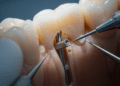

Um dos aspectos mais importantes é o nível de detalhe radiográfico da imagem. Altos níveis de detalhe permitem que professionals identifiquem pequenas fraturas, cáries incipientes e outras anomalias que poderiam passar despercebidas em imagens de menor qualidade. Para isso, é crucial que a tecnologia utilizada seja de ponta e que a técnica de exposição seja ajustada corretamente.

Outro fator vital é a densidade e o contraste da radiografia. A densidade refere-se ao grau de escuridão da imagem, enquanto o contraste se refere à diferença entre áreas claras e escuras. Para um diagnóstico eficaz, a densidade deve ser média, o que permite uma visualização clara dos tecidos moles e duros. Uma imagem com contraste adequado realça os detalhes necessários para a análise, evitando confusões que podem surgir de imagens excessivamente claras ou escuras.

Para determinar se uma radiografia é de qualidade, os profissionais podem avaliar alguns aspectos técnicos. Verifique se a imagem é livre de artefatos, que podem distorcer a visualização. Imagens nítidas, com definição clara das bordas, são essenciais. Além disso, a localização correta das estruturas anatômicas é crucial. Por exemplo, elementos como raízes dentárias e seios maxilares devem aparecer de forma adequada. Uma radiografia bem posicionada irá contribuir para um diagnóstico mais assertivo.